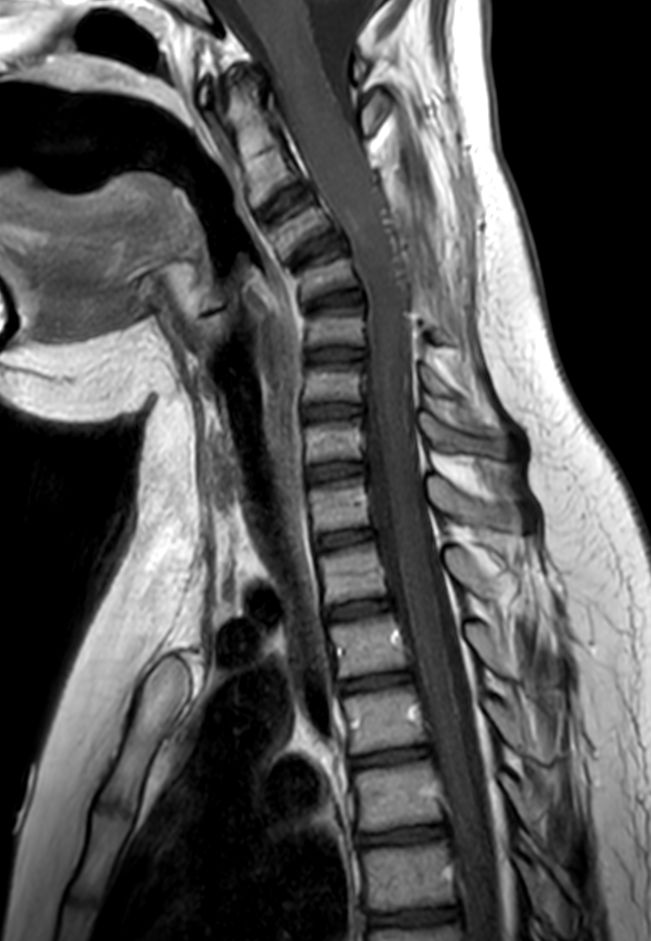

Sagittal T2w TSE (C-Spine)